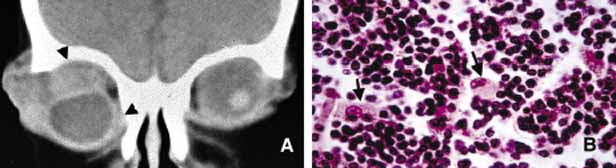

In cases of microphthalmos and anophthalmos the orbit may be well formed but does not develop to a full adult volume. The mechanism by which the presence of the globe effects the growth of the orbit is not well understood. Microphthalmos may be associated with a colobomatous cyst as a result of the abnormal closure of the embryonic optic fissure leading to the prolapse of neuroectodermal tissues into the orbit (Fig. 1) This cystic structure may increase rapidly in size to overshadow the abnormal globe and may be confused with a neoplasm. When cystic lesions in the orbit are suspected imaging studies should be performed not only to look for other intracranial abnormalities but also to establish the possible connection of the cyst to the colobomatous globe versus to abnormally formed meninges.11 Macrophthalmos (buphthalmos) may also rarely develop as a congenital anomaly in patients with Sturge-Weber syndrome and rarely in neurofibromatosis type I.

Fig. 1 Congenital lesions. A very large cystic teratoma of a 1-month old child (A). B. Histology of this lesion that contains a variety of tissues, endodermal, ectodermal, and mesenchymal. An orbital cyst (C) in an orbit containing micro-ophthalmic globe. C, D. The protrusion of the cyst inferiorly creates a mechanical lower lid ptosis that narrows the right maldeveloped conjunctival sac even further. Axial and sagittal CT scan showing a meningoencephalocele (ME) occupying the entire orbit (E). The histopathologic examination of the lesion revealed both meningeal (M) and brain (B) tissues (F). The high-power histopathology reveals ciliated ependymal cells lining some of the cystic spaces (arrowhead) (G).